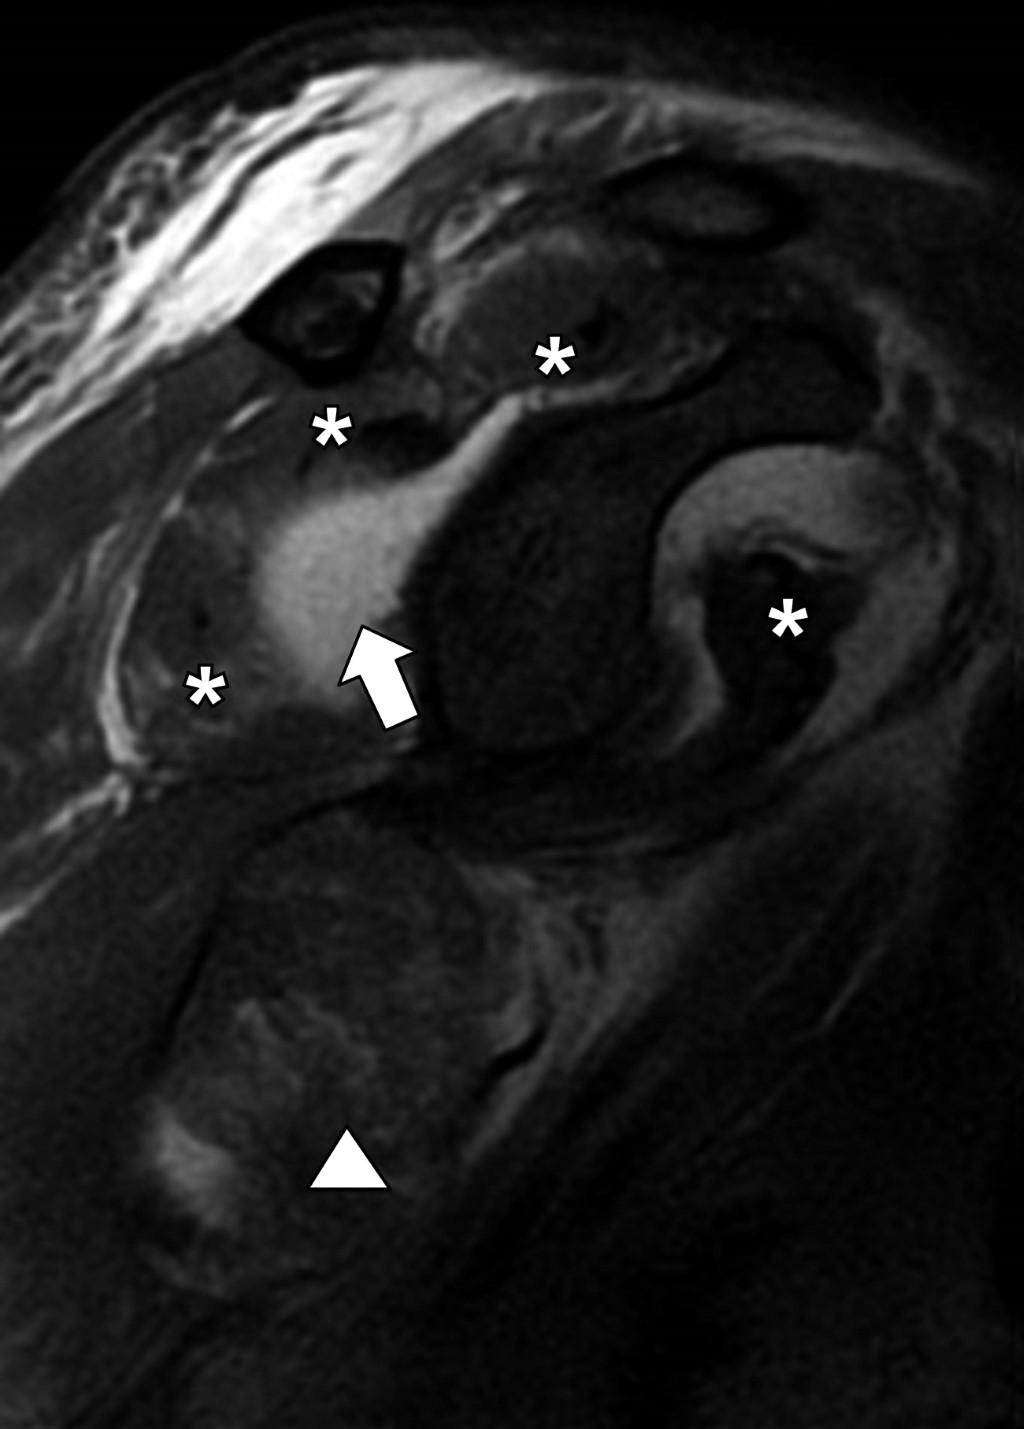

Multifragmentary proximal humerus fracture, the importance of MRI assessment

Proximal humerus fractures represent 45 to 50% of humeral fractures, and the main risk factors are falls, age, osteoporosis, and high-impact sports. The initial diagnostic method for assessing bone structures is radiography, which can be complemented with a tomographic study to assess the fracture line and associated characteristics. In multi-fragmentary fractures with complex lines, the trend of using magnetic resonance imaging is on the rise, as it allows the evaluation of myotendinous and ligamentous structures, which are limitedly evaluated in studies based on ionizing radiation.

Figure 3